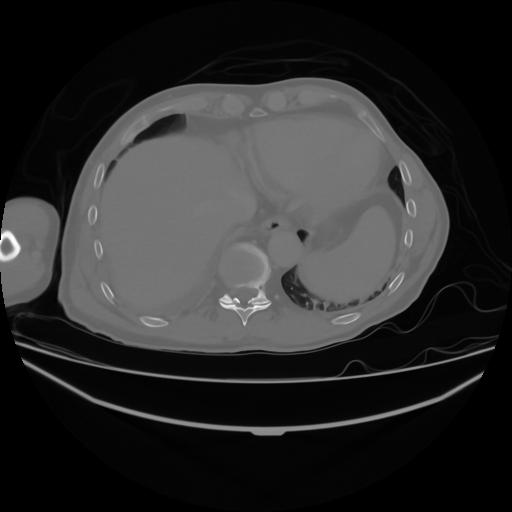

4 CUERPO,CE,Axial,3.0,CUERPO,,